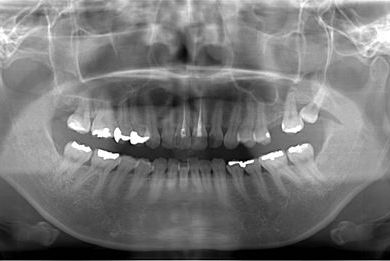

セラミックの症例写真 SHINBI

インプラント矯正治療+セラミック治療

| 性別/年齢 | 女性 / 35歳 | ||||||||||||||||||||||||||||||||

| 主訴 | 歯並び(乱ぐい歯、出っ歯)と歯の色が気になる。 | ||||||||||||||||||||||||||||||||

| 治療方針 | 左上の第一大臼歯がすでに抜歯され欠損の状態で来院されました。デンタルインプラント、あるいはブリッジで補綴するよりも、上あごが突出していること、乱杭歯があることより、矯正治療を第一選択としました。上下第一小臼歯を4本抜歯してその隙間を利用し、治療していきました。抜歯スペースをすべて効率的に利用したいため、上顎左右、下顎左側1本の計3本のインプラントアンカーを使用します。左上は第二大臼歯、智歯を利用しています。今後保定装置の針金は一生装着予定です。上顎の中切歯は左右とも人工的にかぶせものをしています。初診の歯牙変色がなくなり、審美的にもとてもよくなりました。 | ||||||||||||||||||||||||||||||||

| 治療内容 | インプラント矯正(唇側矯正ホワイト、審美ワイヤー、左右上顎第一小臼歯抜歯、上顎インプラントアンカー) | ||||||||||||||||||||||||||||||||